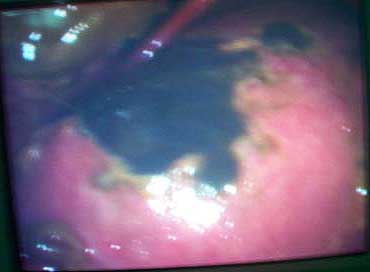

Now what I have not told so far: At about three weeks after the injury when patient had recovered from the problems described above developed acalculous cholecystitis. As he was being prepared for surgery he suddenely collapsed and went into shock. Required resuscitation and inotropic support. After vital signs were stable he was taken up for laparoscopic cholecystectomy. On introducing the scope it was found that there was a gangrenous gall bladder with lots of inflammation all around. It was converted to an open cholecystectomy. Ventillated post op. Patient's ext fix on pelvis was removed after six weeks and ambulated with walker. Had developed a deep sacral pressure sore. Discharged with home care of pressure sore and ambulation with support. Now at about three weeks the femur is uniting, pelvis stable and the pressure sore healing. Patient changed to axillary crutches from walker.

My question to the list: How often do you see acalculous cholecystitis following pelvic fracture? Any other comments?? Laparoscopic picture of gall bladder and present x-rays attached.

In my experience as general surgeon/traumatologist with ICU license, we see such patients rarely, but only in the very sick patients with multiple organ system failure or multiple trauma, as in the presented case. Literature tells us : 3-5 % of such cases, so in a big trauma center probably once per year. No specific relation with the pelvic ring fracture, just in relation to the multiple organ disease. And then the gallblader looks exactly like the pictures you presented: the ongoing infection causes ischaemia and necrosis.